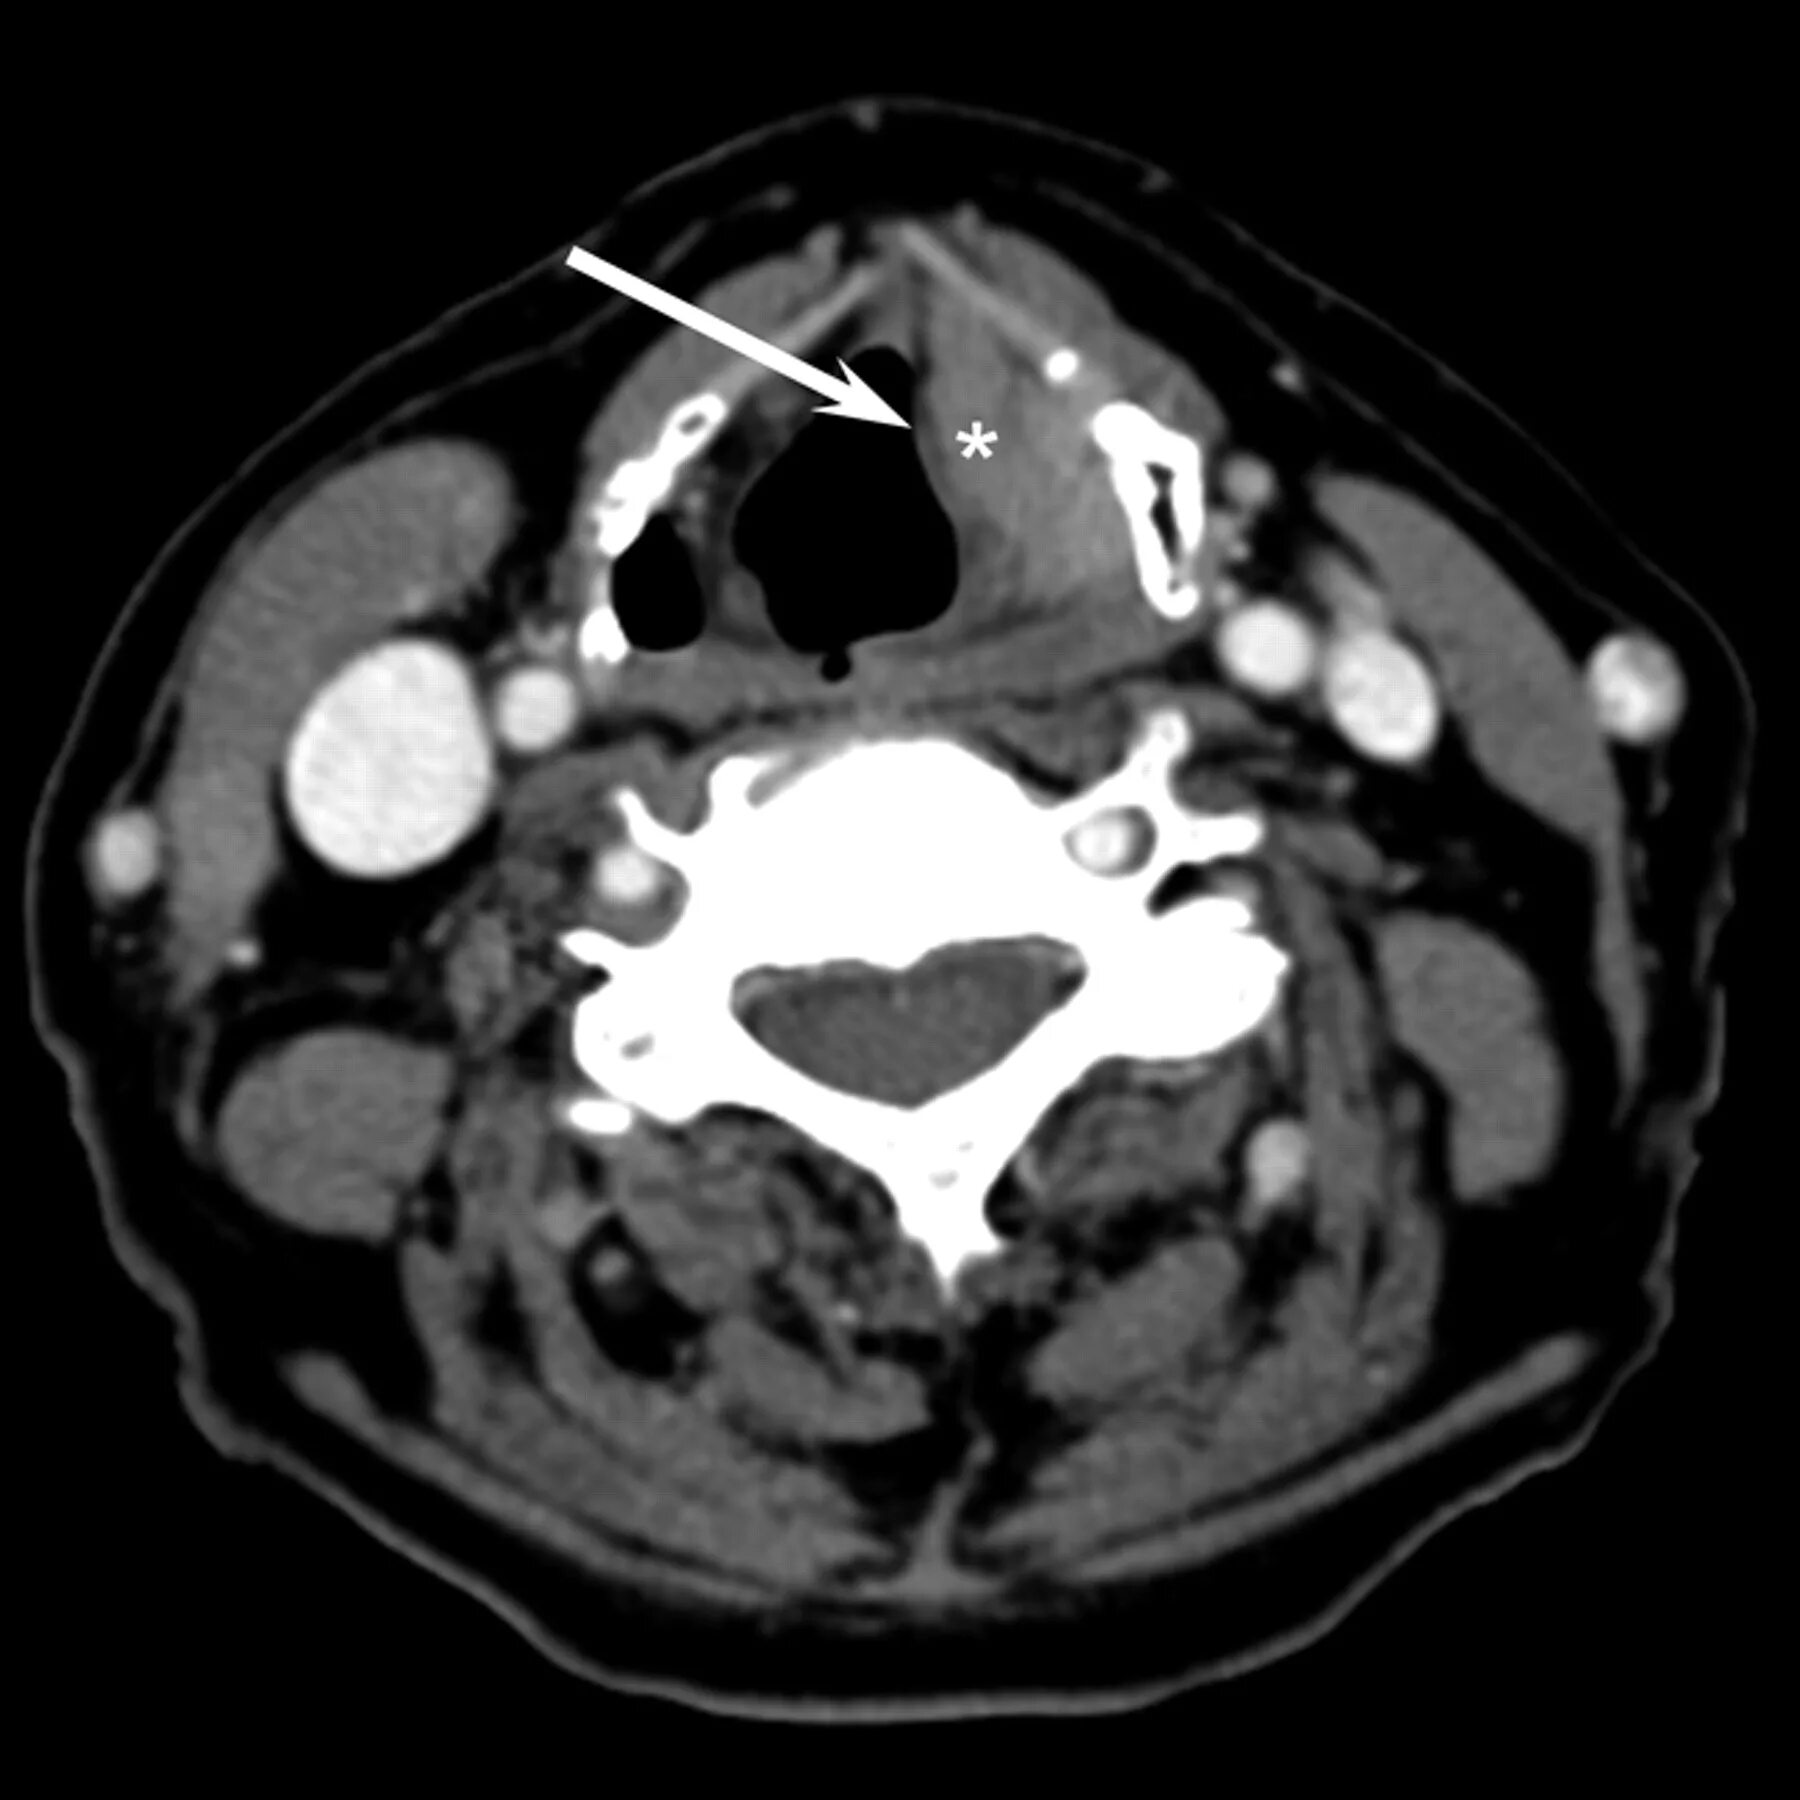

Миндалины на кт